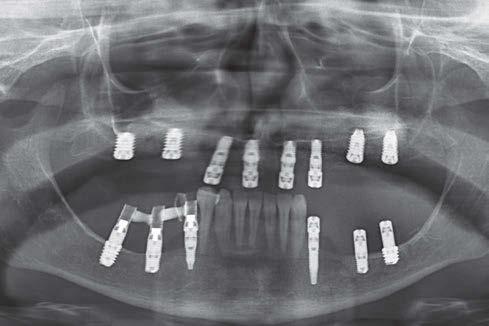

Elevación de seno transcrestal con implantes cortos versus elevación de seno convencional con ventana lateral

Estudio retrospectivo comparativo a boca partida

Ya que ambas técnicas quirúrgicas siguen hoy en día en pleno auge, aunque las indicaciones para cada una de ellas han evolucionado en el tiempo, quedando la elevación convencional únicamente indicada hoy en día en aquellos casos de 1-2 mm de volumen óseo residual (donde es muy complejo estabilizar un implante corto por elevación transcrestal), creemos útil poder comparar la evolución de ambos procedimientos en el tiempo, a ser posible en un mismo paciente, donde el resto de variables que puedan afectar al seguimiento sean iguales, y, por lo tanto, la comparación sea más útil. Por ello, hemos realizado un análisis retrospectivo de pacientes en los que se han realizado los dos procedimientos, uno en cada cuadrante superior y ver la evolución en el tiempo de los implantes insertados en cada caso. Con esta idea en mente, hemos llevado a cabo un estudio retrospectivo que evaluase estos factores, y que se detallan a continuación.

MATERIAL Y MÉTODO

Fueron reclutados de forma retrospectiva pacientes en los que se hubiesen realizado ambas

técnicas de abordaje de seno maxilar: elevación convencional o la inserción de implantes cortos y extra-cortos mediante elevación transcrestal, desde enero de 2010 en adelante. Todos los pacientes fueron estudiados antes de la inserción de los implantes mediante modelos diagnósticos, exploración intraoral y realización de un TAC dental (Conebeam) analizado posteriormente mediante un software específico (BTI-Scan II).